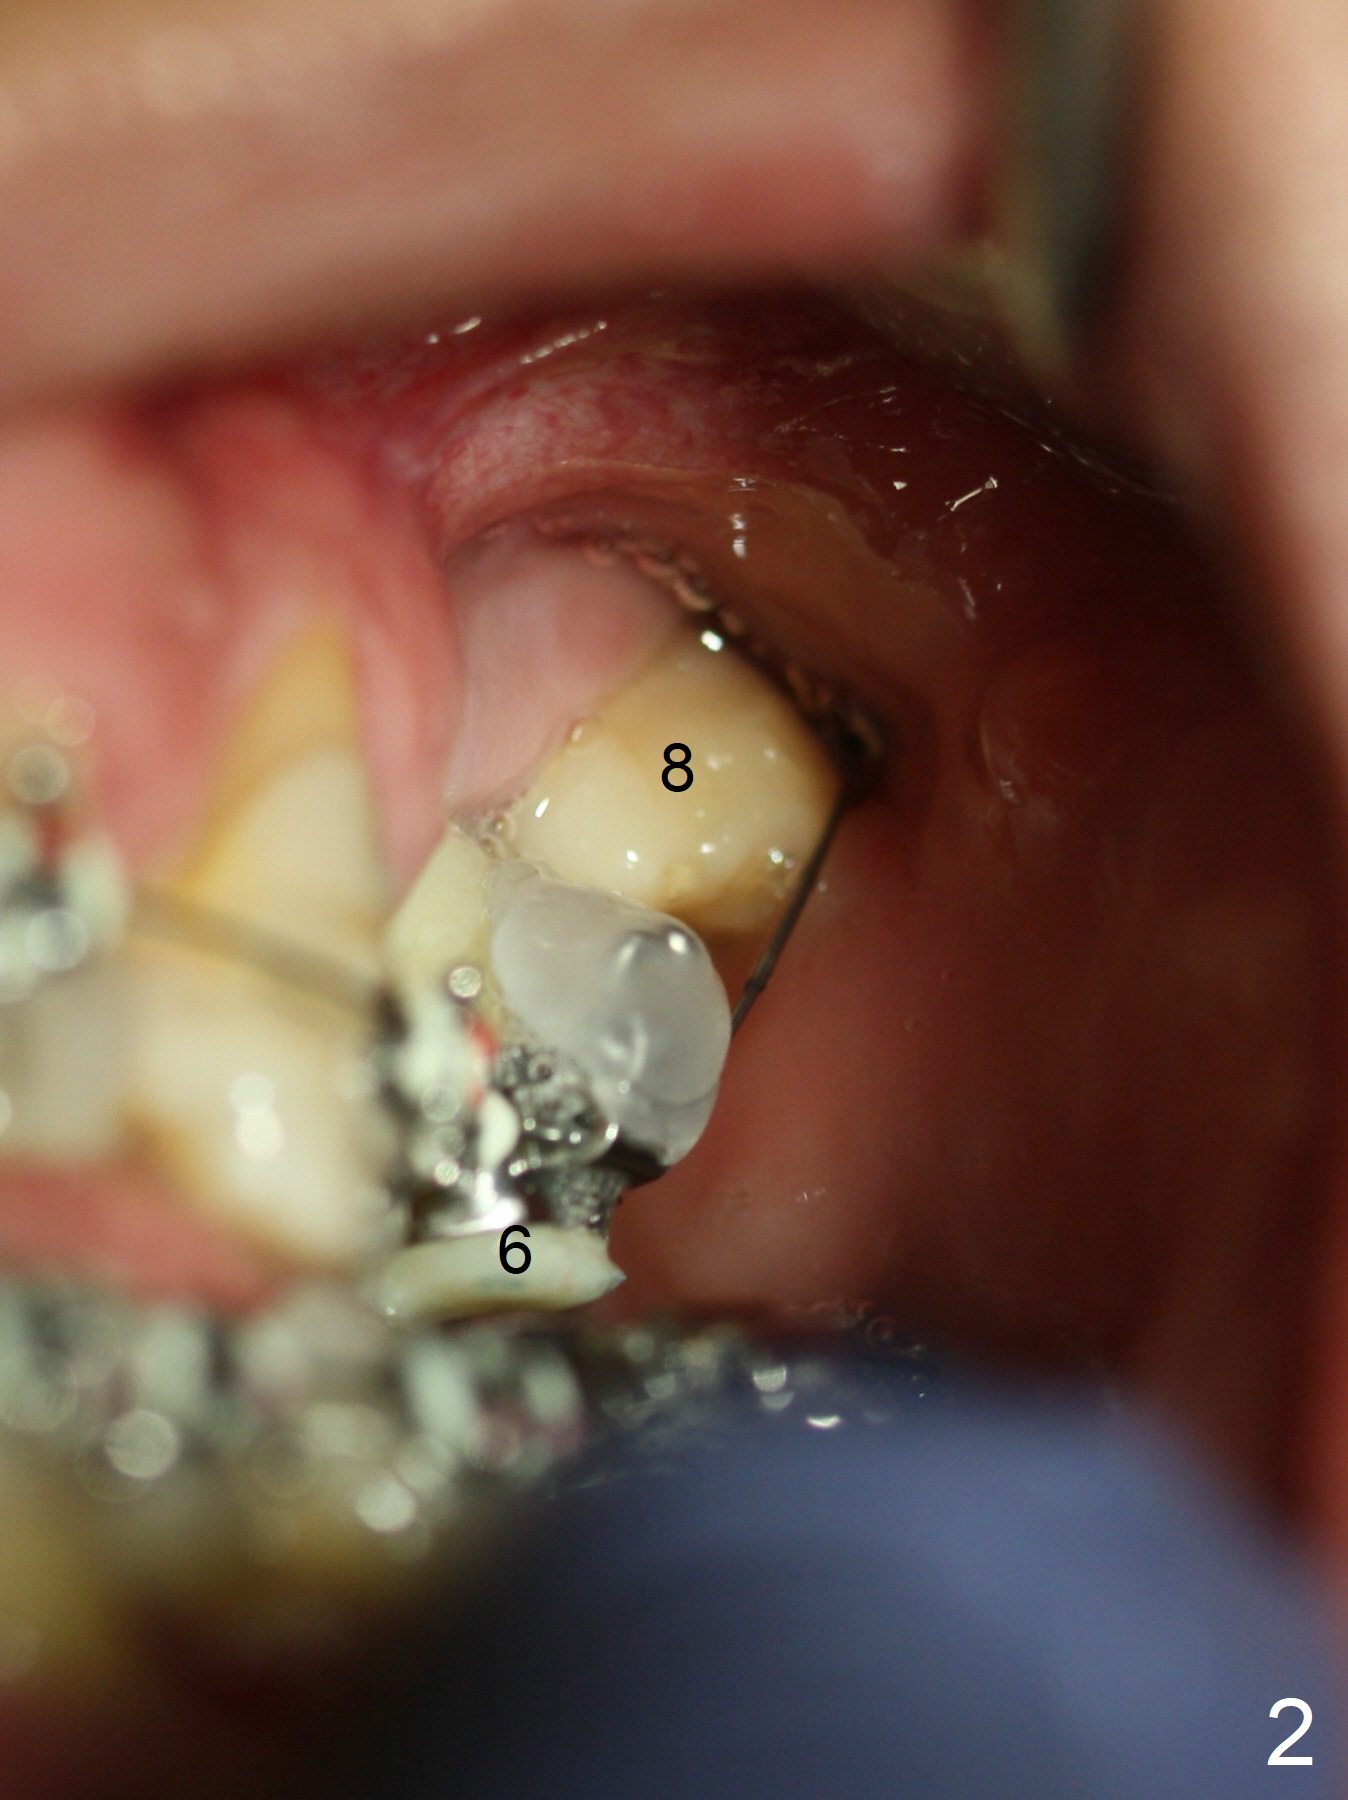

Extrusion of UL8

The provisional at UL6 (implant, as an anchor) is refabricated with normal overjet with LL6 prior to bracketing and banding for comprehensive orthodontics. There is discrepancy of bracketing/banding between UL 6 and 8 (Fig.1,2 (12, 14 niti wires (upper and lower arches)). The upper wire is also roller-coaster between UL3 and 6 (Fig.3).